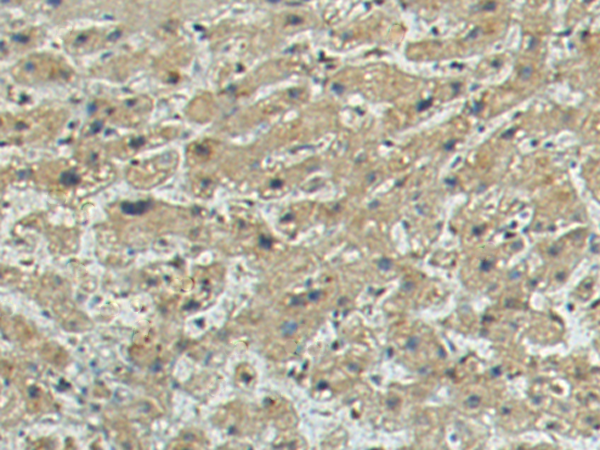

IHC positive control: |

Human liver cancer |

IHC Recommend dilution: |

150-300 |